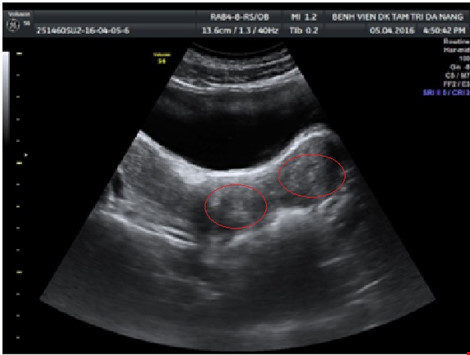

Sau khi được nhập viện, bé được thông tiểu. Kiểm tra qua đường trực tràng có khối căng to đè vào trực tràng và kết quả siêu âm thấy khối tụ máu lớn 140x60mm, lan từ tử cung đến âm đạo, buồng trứng. Thận phải chỉ có một quả thận.

Hình ảnh siêu âm cho thấy 2 tử cung đều dị dạng (Ảnh: BV cung cấp) |